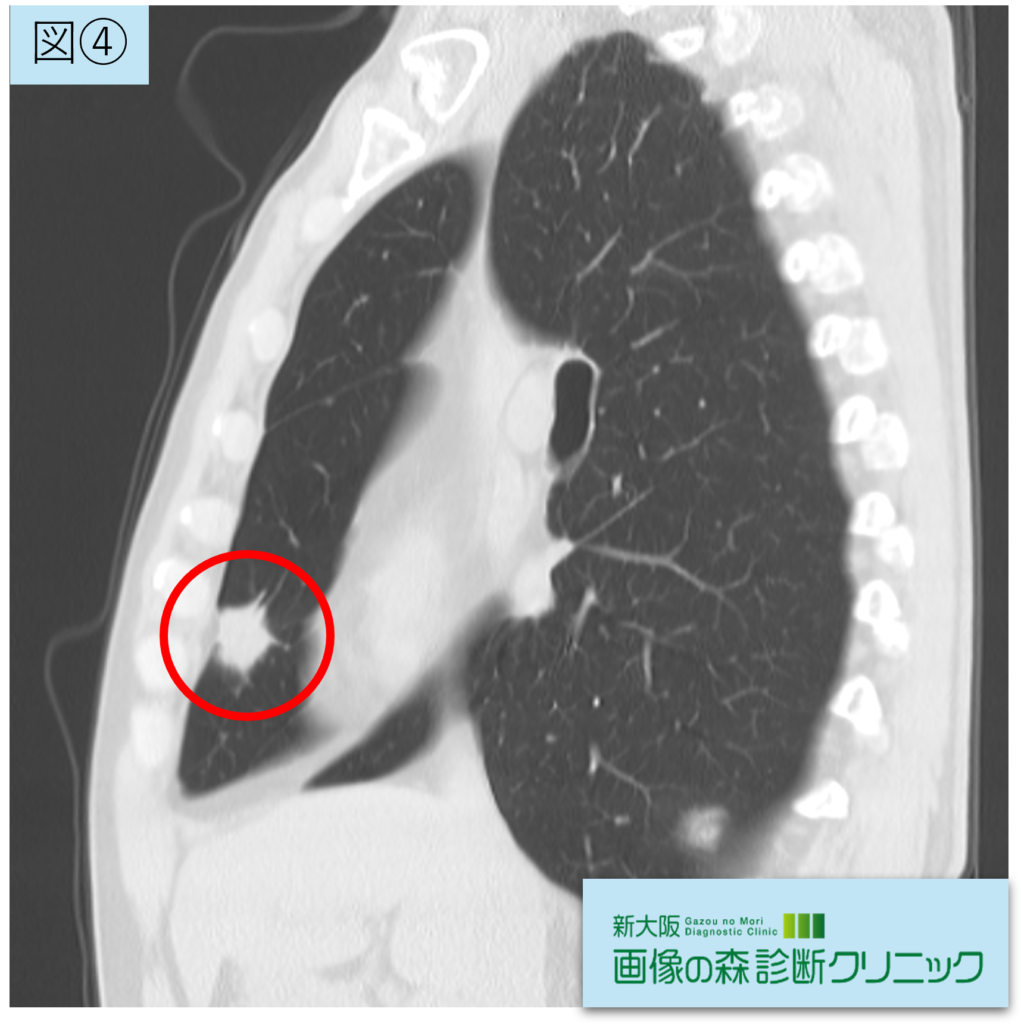

腫瘍画像(矢状断像)

図②③④:腫瘍画像(赤〇が腫瘍部位です)

右肺中葉に21.5mmの腫瘍性陰影を認めます。辺縁不整(スピクラ)の充実性腫瘤を認め、悪性を疑う所見です。